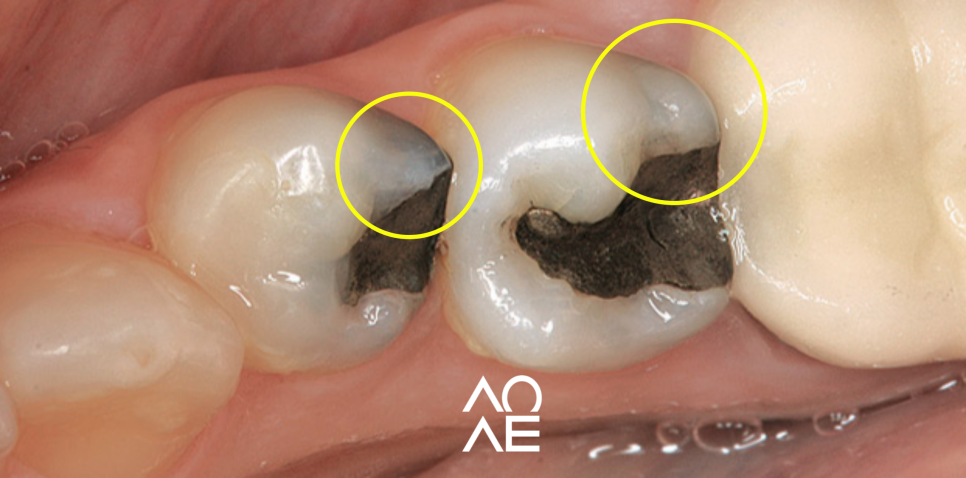

일단 육안으로 보셨을 때 충치가 아니라

치료 했던 부위가 검게 보인다면

'아말감'으로 치료를 받으셨을 확률이 높아요.